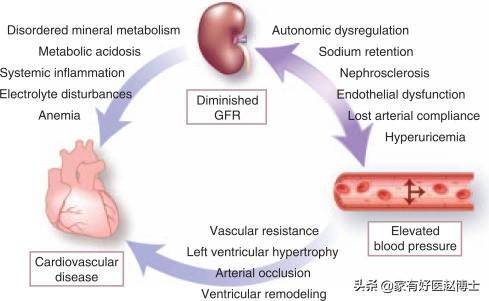

L'une des complications les plus graves de l'hypertension est la néphropathie hypertensive et, comme nous le savons tous, le déclin de la fonction rénale dans la néphropathie est plus susceptible de provoquer une augmentation de la pression artérielle. En d'autres termes, le rein est à la fois l'organe cible des dommages causés par l'hypertension, mais aussi un organe important pour la cause de l'hypertension. On dit donc qu'il s'agit de deux frères difficiles qui s'aident mutuellement à être mauvais.

La relation entre l'hypertension et les reins est à la fois étroite et complexe, et les dommages causés aux reins par l'hypertension comprennent principalement : ① la néphrosclérose : au début de l'évolution des patients atteints d'hypertension essentielle légère et modérée, pendant une période assez longue, il n'y a pas de changements structurels et fonctionnels évidents au niveau des reins, seulement le spasme des petites artères rénales et l'affaiblissement de la fonction d'autorégulation rénale, comme la réduction de la capacité d'adaptation à des états non physiologiques tels qu'une charge élevée en sodium et une expansion volumique aiguë. Après un certain temps, en raison du spasme continu des petites artères rénales, celles-ci subissent une dégénérescence, un durcissement et un rétrécissement, et les unités rénales subissent une atrophie et une sclérose dues à l'ischémie, ce qui nuit gravement à la fonction rénale. L'hypertension primaire se manifeste d'abord par des lésions des tubules rénaux et des changements fonctionnels, le patient se manifeste par une nycturie accrue, les tests de laboratoire révèlent une petite quantité de protéines dans l'urine, principalement des protéines à petites molécules (la β2 microglobuline est un trait caractéristique), la gravité spécifique de l'urine est réduite et la capacité d'acidification de l'urine est diminuée. En général, l'hypertension primaire continue à se développer régulièrement et une petite artériosclérose rénale légère à modérée peut apparaître après 5 à 10 ans. ② athérosclérose de l'artère rénale : l'hypertension est un facteur causal important de l'athérosclérose, et l'artère rénale est un site privilégié de l'athérosclérose. L'artériosclérose rénale réduit le flux sanguin rénal, active le système rénine-angiotensine-aldostérone, provoquant une vasoconstriction, une rétention de sodium et une nouvelle élévation de la pression artérielle, formant ainsi un cercle vicieux. Environ 7 % des patients atteints d'hypertension primaire présentent une augmentation soudaine et progressive de la pression artérielle au cours de la maladie, qui se transforme en hypertension maligne. Lorsque la pression artérielle évolue vers une hypertension aiguë, une nécrose fibrinoïde des petites artères rénales se produit, et les reins sont gravement ischémiés, avec une détérioration rapide de la fonction rénale et une progression rapide vers l'urémie.

Parmi les adultes de plus de 18 ans en Chine, au moins une personne sur quatre souffre d'hypertension artérielle, et l'incidence de l'hypertension artérielle continue d'augmenter. Le rein est un organe étroitement lié au développement de l'hypertension. Nous savons tous que le rein est responsable de la régulation de l'équilibre eau-sel dans l'organisme (équilibre liquide-électrolyte), l'augmentation de l'eau et du sel dans l'organisme entraîne facilement une augmentation de la pression artérielle ; et l'augmentation de la pression artérielle affecte l'hémodynamique des reins, entraînant des lésions rénales. C'est pourquoiLes reins sont à la fois l'organe régulateur de la pression artérielle et l'organe cible des lésions dues à l'hypertension, et il existe un cercle vicieux entre l'hypertension et les lésions rénales.。

L'hypertension à long terme, si elle n'est pas contrôlée, peut conduire à l'athérosclérose des petites artères rénales, à l'hypoplasie rénale, à l'hypoplasie rénale, à une nouvelle augmentation de la pression artérielle, ce qui entraîne un cercle vicieux, et finalement, la fonction rénale continue à se détériorer, devenant une urémie.